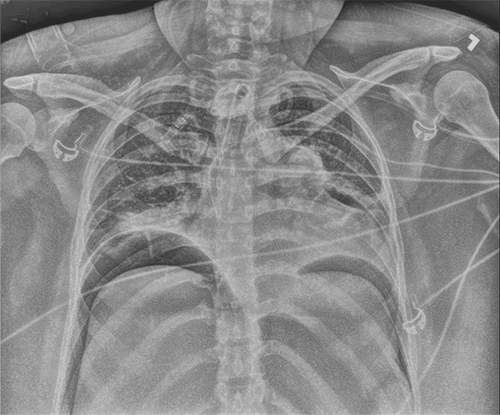

Within 30 minutes of arrival to the SICU, the patient’s abdomen was noted to be distended and firm. Her peak inspiratory pressures (PIP) were elevated, ranging between 55 to 60, and she was hypoxic with oxygen saturation in the 70s and 80s. Arterial blood gas (ABG) revealed a pH of 7.32, PaCO2 of 70, and bicarbonate level of 35. The PAO2/FiO2 ratio was 87. A chest X-ray (CXR) (Figure 1) showed the tracheostomy tube placed in the right mainstem bronchus. An urgent bedside tracheostomy exchange was performed by the ENT, replacing the tube with a shorter one. A subsequent CXR also revealed pneumoperitoneum, with free air observed under both hemidiaphragm, a finding that was confirmed by abdominal X-ray (AXR) (Figure 2).

Figure 1. Postoperative Chest X-ray. Published with Permission

Right mainstem tracheostomy and free intraperitoneal air under bilateral hemidiaphragm is indicated